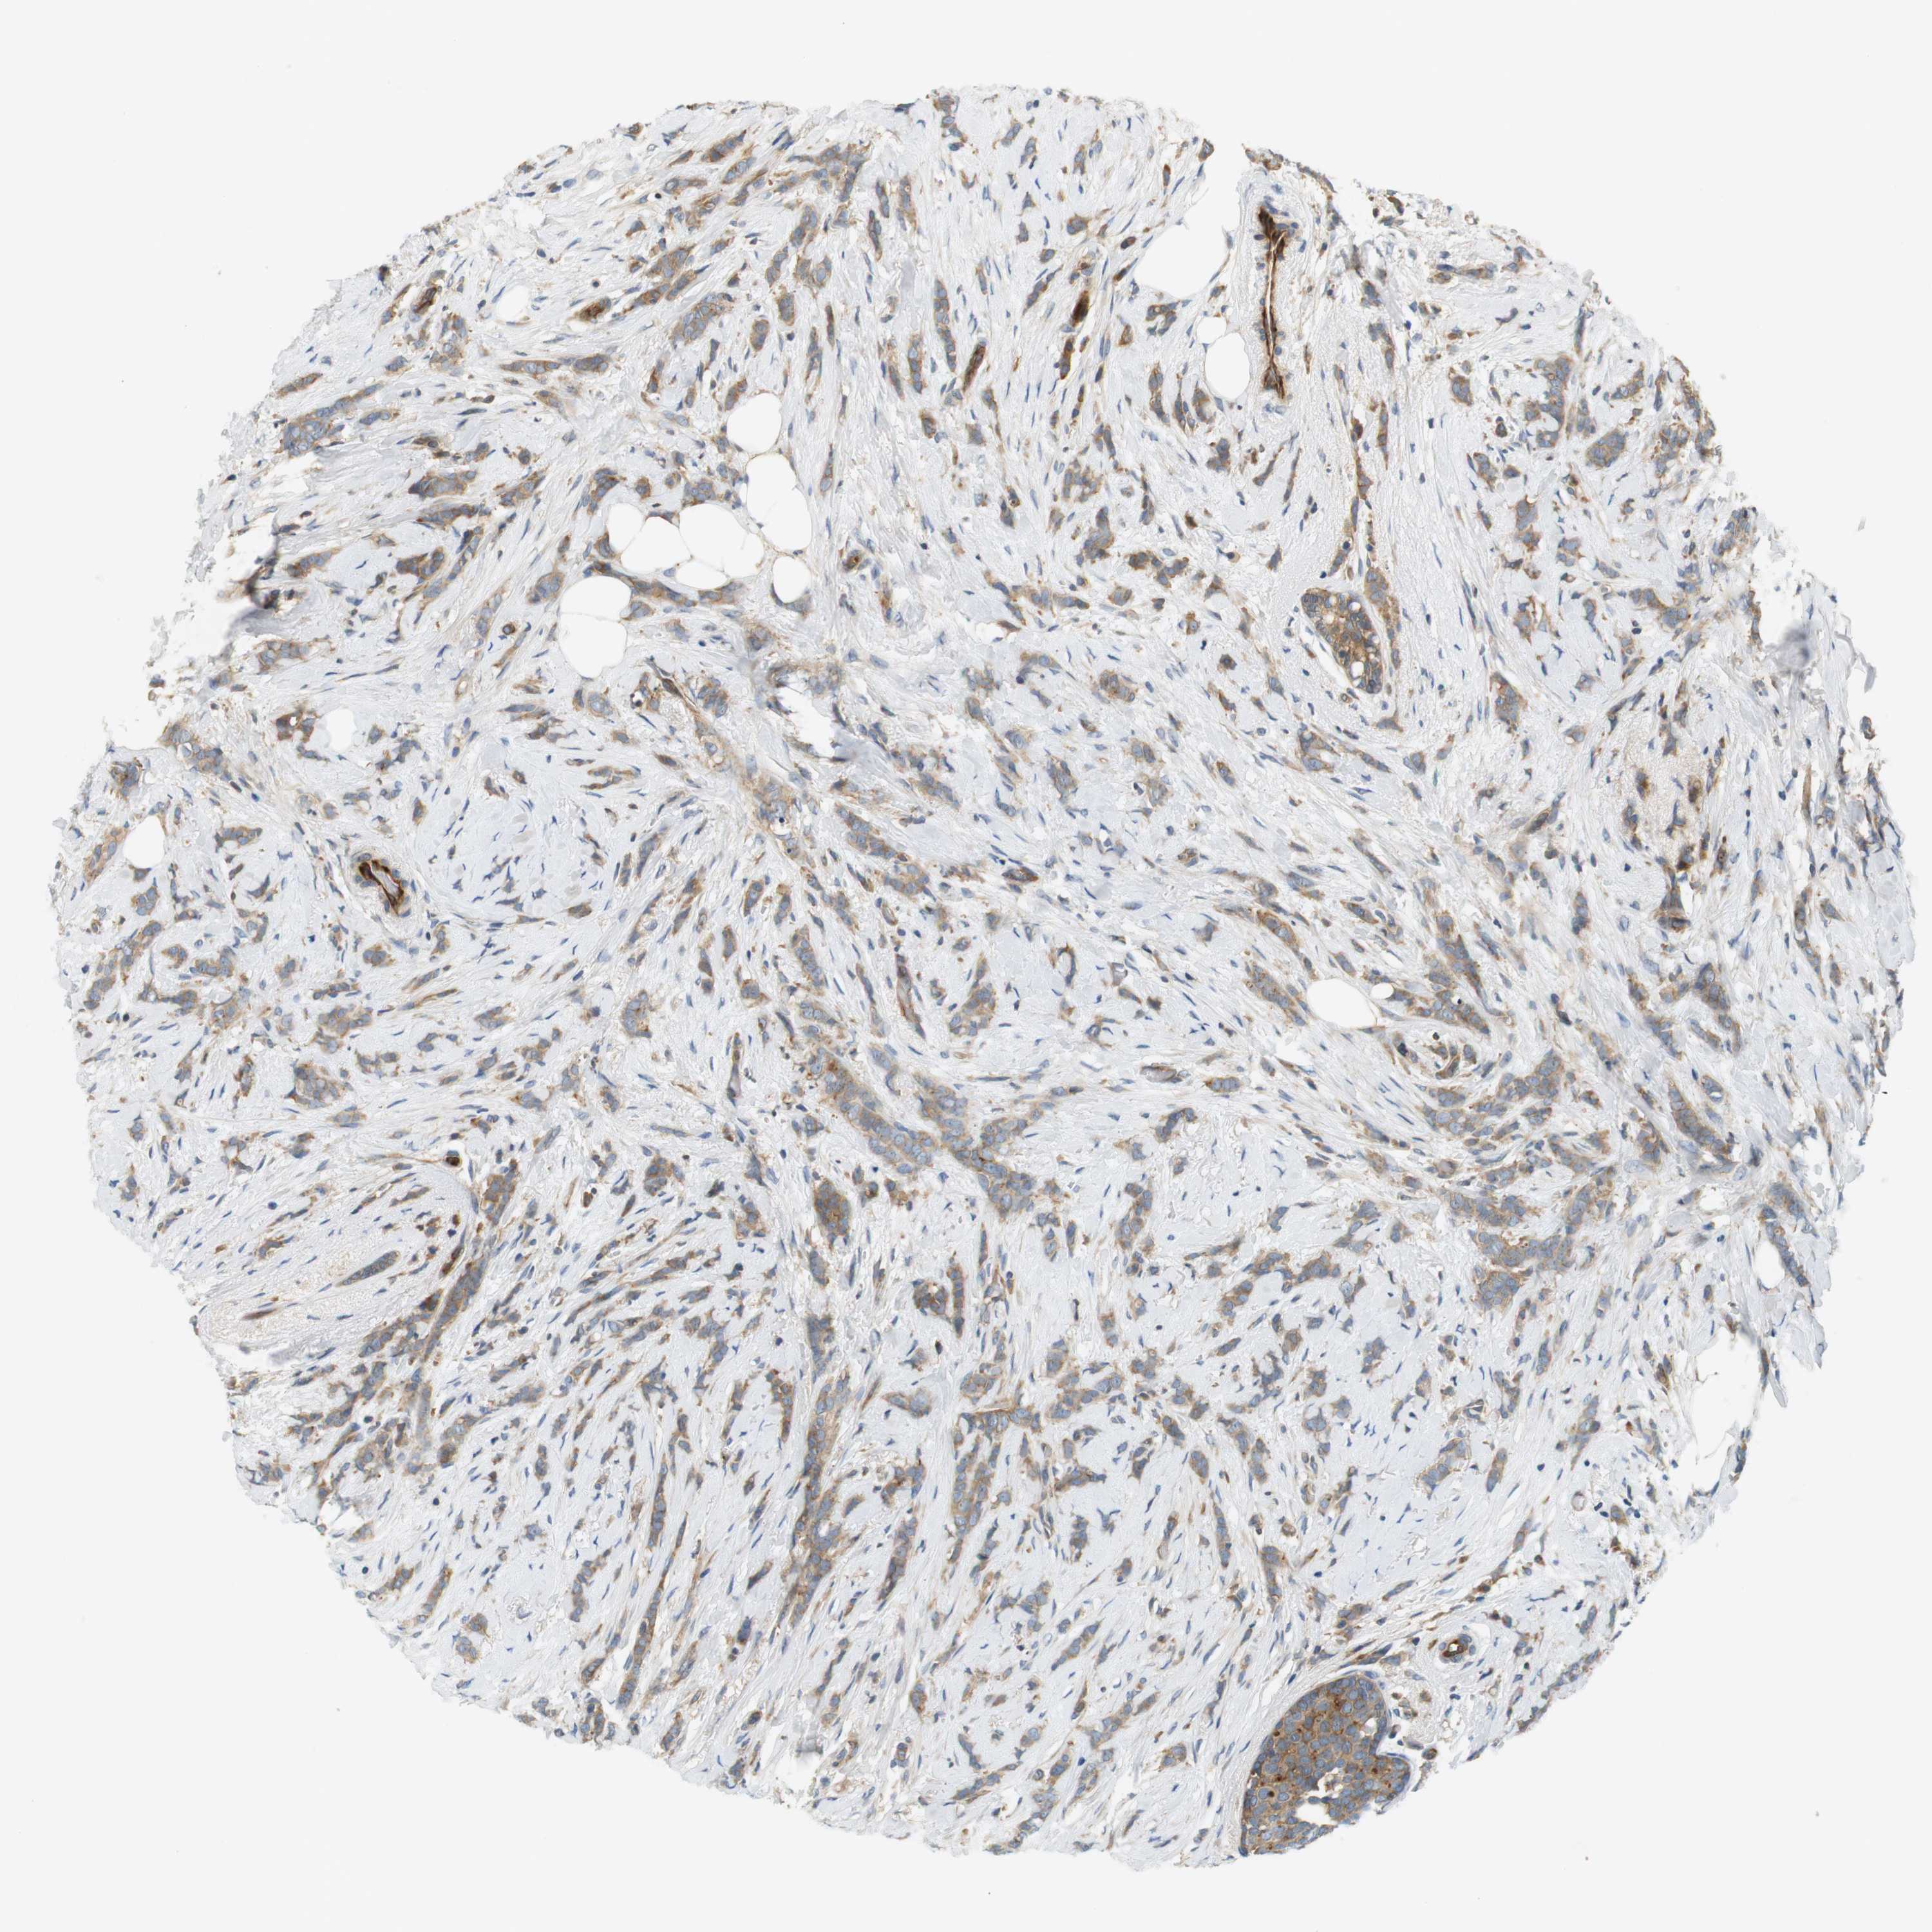

CANCER BREAST CANCER Show tissue menu

BRCA TCGA BRCA VALIDATION PROTEIN EXPRESSION